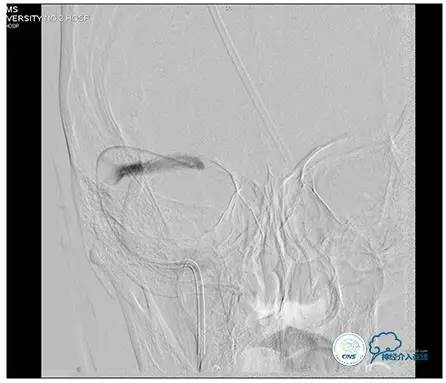

术后右侧ICA造影

术后远、近端压力差为:0

术后右侧ICA斜位